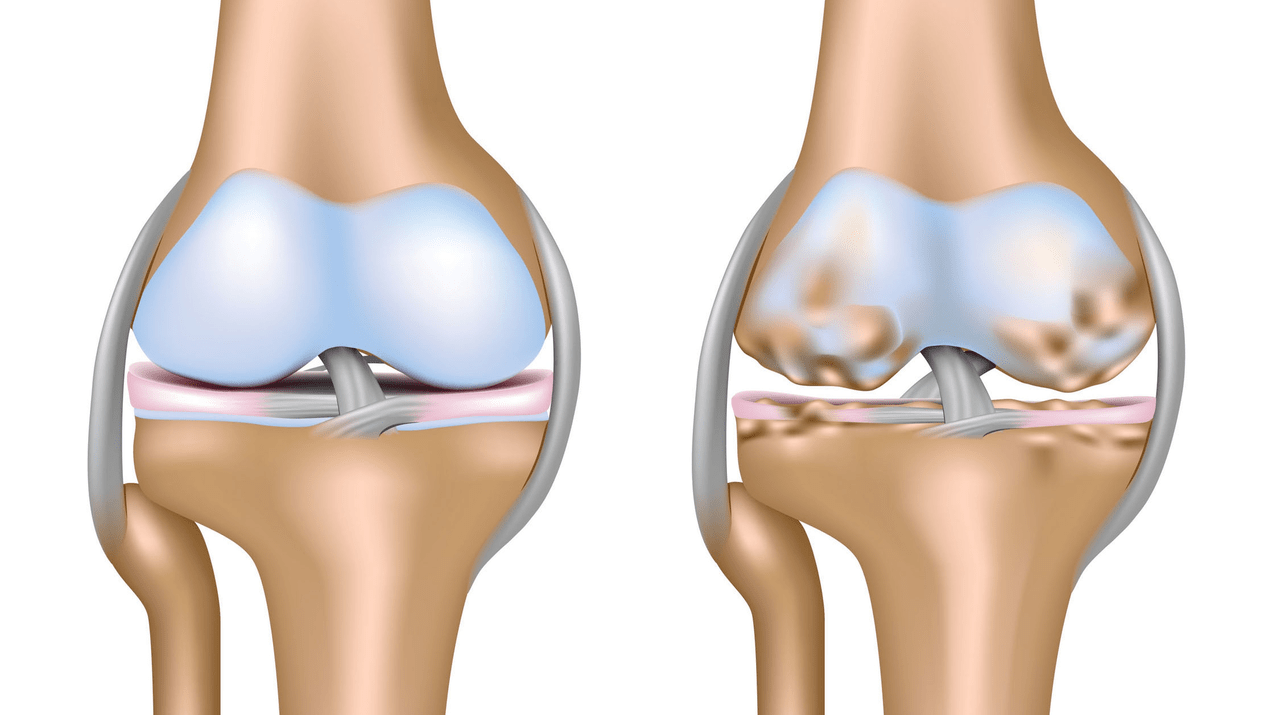

Arthrosis of the knee joint (gonarthrosis)is a chronic progressive disease of the knee joints with injury, thinning and destruction of its cartilaginous part (articular surfaces of the femur and tibia), in addition to damage to the subchondral bone.It has been proven by studies (arthroscopy and magnetic resonance imaging) that in addition to damage to the articular cartilage, the menisci and synovial membrane are involved in the process.Gonarthrosis is one of the most common orthopedic pathologies.There are its synonyms - osteoarthritis (OA), deforming arthrosis.The disease is an important socioeconomic problem, as it is widespread and significantly worsens patients' quality of life due to constant pain and, in addition, becomes a cause of high disability.

Until the mid-eighties of the last century, there was no unified definition of the disease.Only in 1995 did the osteoarthritis committee of the American College of Rheumatology characterize the disease as the result of mechanical and biological factors that lead to an imbalance between the processes of degradation and synthesis of the extracellular matrix of articular cartilage.As a result, disintegration and degeneration of fibers occur, cracks, osteosclerosis and compaction of the cortical layer of the subchondral bone form, osteophytes grow and subchondral cysts form.

In arthrosis (osteoarthrosis), in addition to the progressive destruction of cartilage, loss of elasticity and shock-absorbing properties, bones are gradually involved in the process.Under load, sharp edges (exostoses) appear, which are mistakenly considered “salt deposits” - in classic arthrosis, salt deposition does not occur.As osteoarthritis progresses, it continues to “eat” the cartilage.Then the bone becomes deformed, cysts form, all joint structures are affected and the leg becomes bent.

In the second stage, the cartilage layer becomes noticeably thinner and in some places is completely absent.Osteophytes appear along the edges of the articular surfaces.The qualitative and quantitative characteristics of the synovial fluid of the joint change - it becomes thicker, more viscous, which leads to a deterioration in its nutritional and lubricating properties.The pain is more prolonged and intense, and a grinding sound often appears during movement.There is a mild or moderate restriction of movement and slight deformation of the joint.Taking painkillers helps to alleviate the pain.

Gonarthrosis, stage III

Lack of cartilage in the most affected areas, severe sclerosis (hardening) of the bone, many osteophytes and marked narrowing or absence of the joint space.The pain is almost constant and walking is impaired.Mobility is quite limited and joint deformation is noticeable.NSAIDs, physical therapy and other standard methods of treating knee osteoarthritis are ineffective.